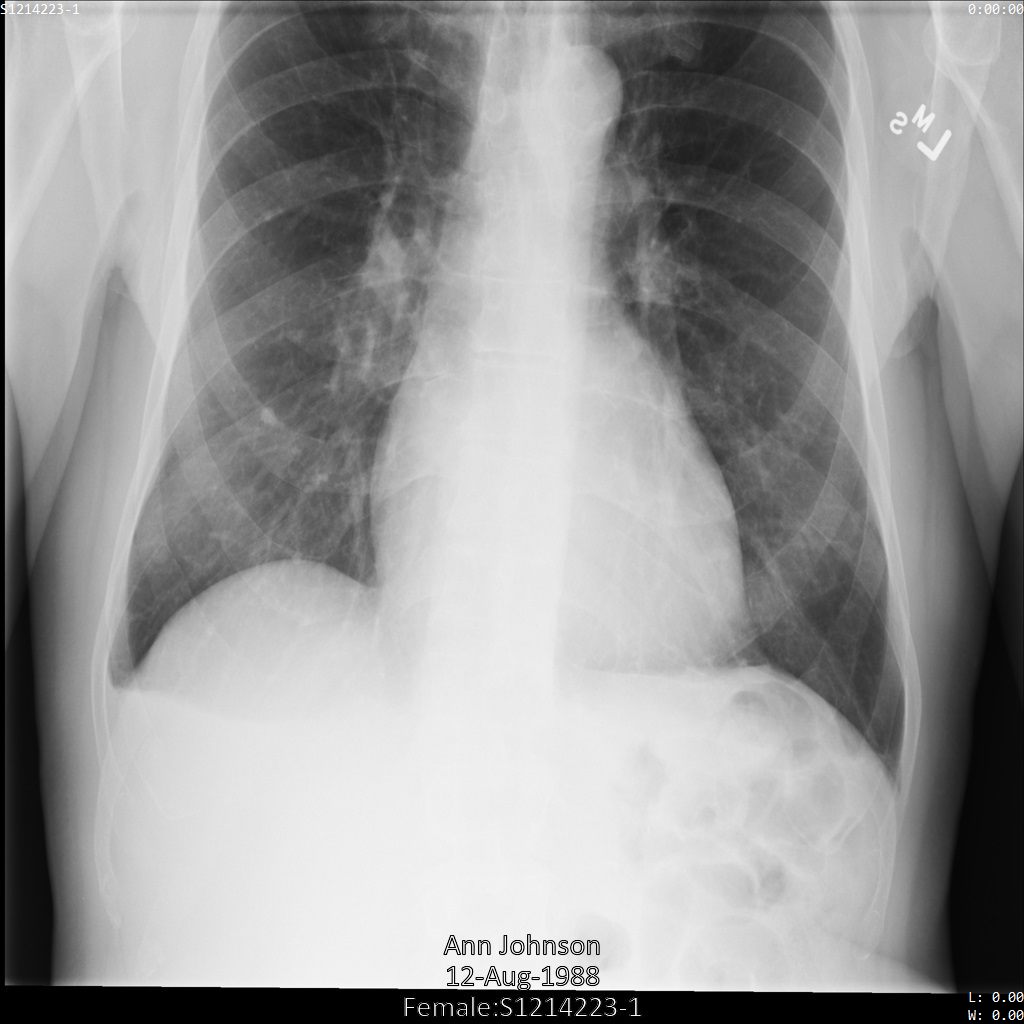

Descripción general de muestras

En las muestras de esta guía, se usa una sola instancia de DICOM, pero también puedes desidentificar varias instancias.

En cada una de las siguientes secciones, se proporcionan ejemplos de cómo desidentificar datos de DICOM mediante varios métodos. Se proporciona un resultado de la imagen desidentificada en cada muestra. En cada muestra, se usa la siguiente imagen original como su entrada:

Puedes comparar la imagen de salida de cada operación de desidentificación con esta imagen original para ver los efectos de la operación.

Después de enviar la imagen a la API de Cloud Healthcare, la imagen aparece de la siguiente manera. Mientras se ocultan los metadatos que se muestran en las esquinas superiores de la imagen, la información de salud protegida (PHI) quemado en la parte inferior de la imagen permanece. Para quitar también el texto quemado, consulta Oculta el texto quemado de las imágenes.